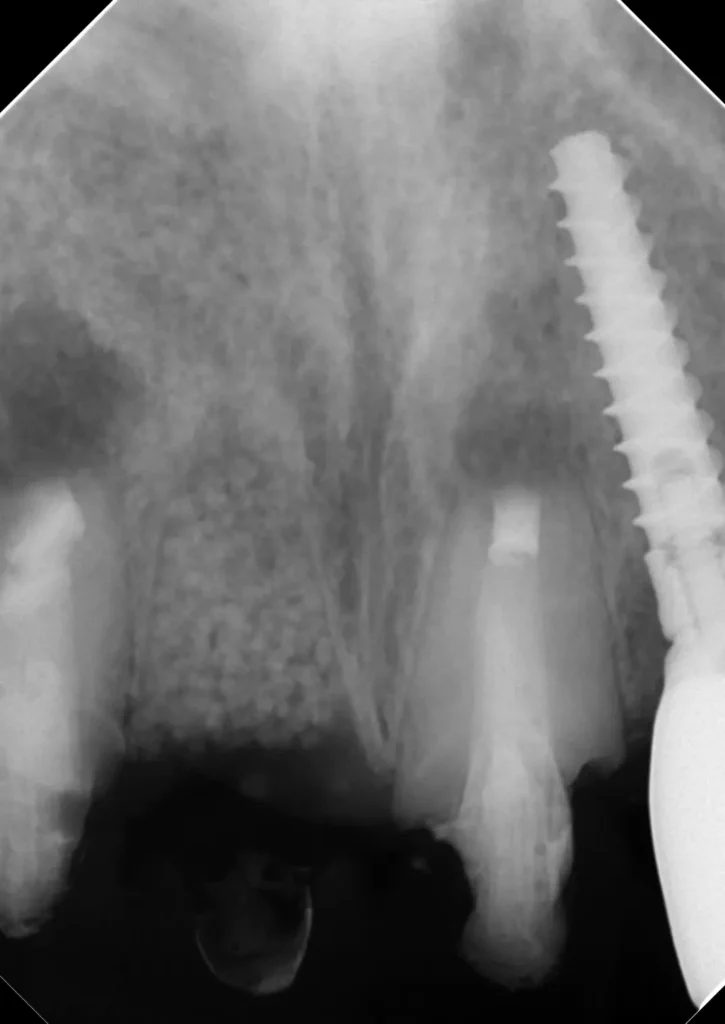

自費根管治療症例6 治療前(外科的歯内療法)

「前歯がなんとなく違和感がある」

初診時

以前の治療の切開の跡がわかります

初診時レントゲン写真

インプラント隣の歯の根の先に人工材料が逸出しています。

初診時レントゲン写真2

右側(向かって左)の歯は以前、他院で外科的歯内療法を受けています

術中レントゲン写真

右側1番(真ん中)の歯は歯根破折のため抜歯になりました(コツ補填材を抜歯窩に充填)

2本とも歯根端切除術を行いました